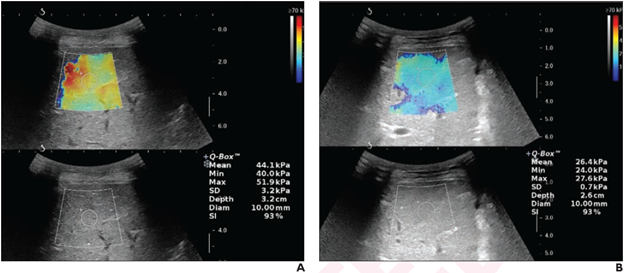

12-Year-Old Boy With Chronic Budd-Chiari Syndrome, Presenting With Recurrent Abdominal Pain and Distention, After Undergoing Left Hepatic Vein Angioplasty. Liver stiffness measurement before (A) and 24 hours after (B) intervention shows a decrease from 44.1 kPa to 26.4 kPa.

“LSM decreased significantly after image-guided intervention for chronic BCS in children, showing a maximal decrease at 24 hours post-intervention,” wrote corresponding author Sanjay Sharma from the department of radiodiagnosis and interventional radiology at the All India Institute of Medical Sciences in New Delhi. “Disease recurrence was typically associated with an increase in LSM, compared with the patient’s prior measurement.”

In the 32 children (28 boys, 4 girls; mean age, 9.0 years) who underwent image-guided intervention for chronic BCS, median LSM was 43.7 kPa at baseline and 22.5 kPa, 18.7 kPa, and 16.7 kPa at 24 hours, one month, and three months, respectively, after intervention. In eight of nine patients with recurrence, LSM was increased, compared with the pre-recurrence measurement.